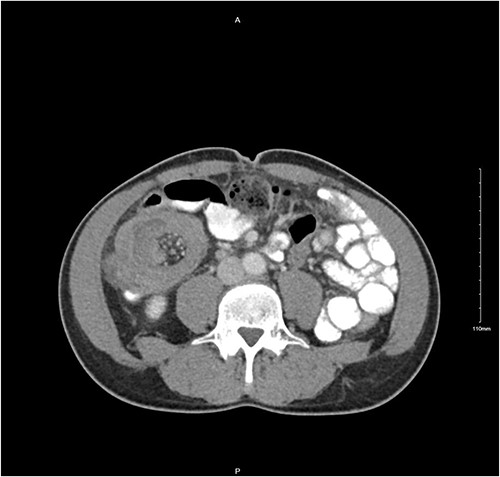

A 56-year-old male was diagnosed with a 4-day history of worsening, cramping left-sided lower abdominal pain and persistent vomiting. The patient had experienced intermittent bouts of similar pain in the previous few months; however, the sustained nature of the pain on this occasion prompted his presentation. Clinical examination elicited lower abdominal tenderness, most marked in the right para-umbilical region. He was an otherwise healthy patient, with no pertinent medical history. Initial investigations revealed a white cell count of 11.78 × 109/L with an associated mild neutrophilia of 9.29 × 109/L. His C-reactive protein was significantly elevated at 130 mg/L, with remaining haematological tests otherwise unremarkable. A computed tomography (CT) scan with intravenous contrast of the abdomen and pelvis was performed which identified a long segment (21 cm) of intussusception involving the distal small bowel, caecum and ascending colon and entirety of transverse colon, including mesentery (Fig. 1). A 5.5-cm hypodense mass was noted within the splenic flexure of the transverse colon which acted as a lead point for intussusception (Fig. 2). There was no pathological small bowel dilatation. Radiologically, the suggested differential diagnosis included gastrointestinal stromal tumour, carcinoid tumour, leiomyosarcoma, lymphoma or benign pathologies such as leiomyoma. The patient proceeded to theatre whereby a formal resection by means of extended right hemicolectomy and primary anastomosis was performed. Histological analysis demonstrated an ileal myxoma to be the causative pathology. The patient had an unremarkable post-operative course and was discharged well 1 week post-operatively.

Transverse CT image of small bowel intussusception into the ascending colon.